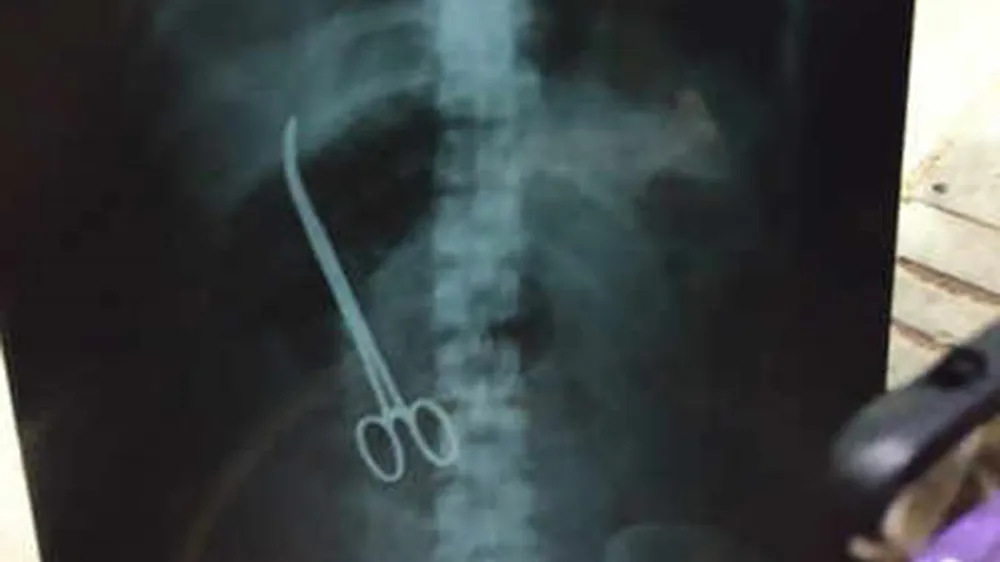

Các bác sĩ của Bệnh viện Y Khoa Nizams (NIMS) tại thành phố Hyderabad, thủ phủ của bang Telangana, thuộc miền Nam Ấn Ðộ, đã thực hiện thành công ca phẫu thuật để lấy một chiếc kéo y tế bị bỏ quên trong bụng một bệnh nhân nữ khi tiến hành ca mổ thoát vị ruột hồi đầu tuần này.

Sau ca phẫu thuật điều trị thoát vị ruột và trở về nhà hôm 7-2, bệnh nhân đã phải nhập viện trở lại ngay trong đêm cùng ngày với tình trạng đau bụng quằn quại. Sau khi siêu âm và phát hiện dị vật bên trong ổ bụng, ca phẫu thuật thứ hai được chỉ định tiến hành trong sáng 9-2. Giám đốc Bệnh viện NIMS, Tiến sĩ K.Manohar, cho biết, hiện sức khỏe bệnh nhân đang hồi phục tốt.